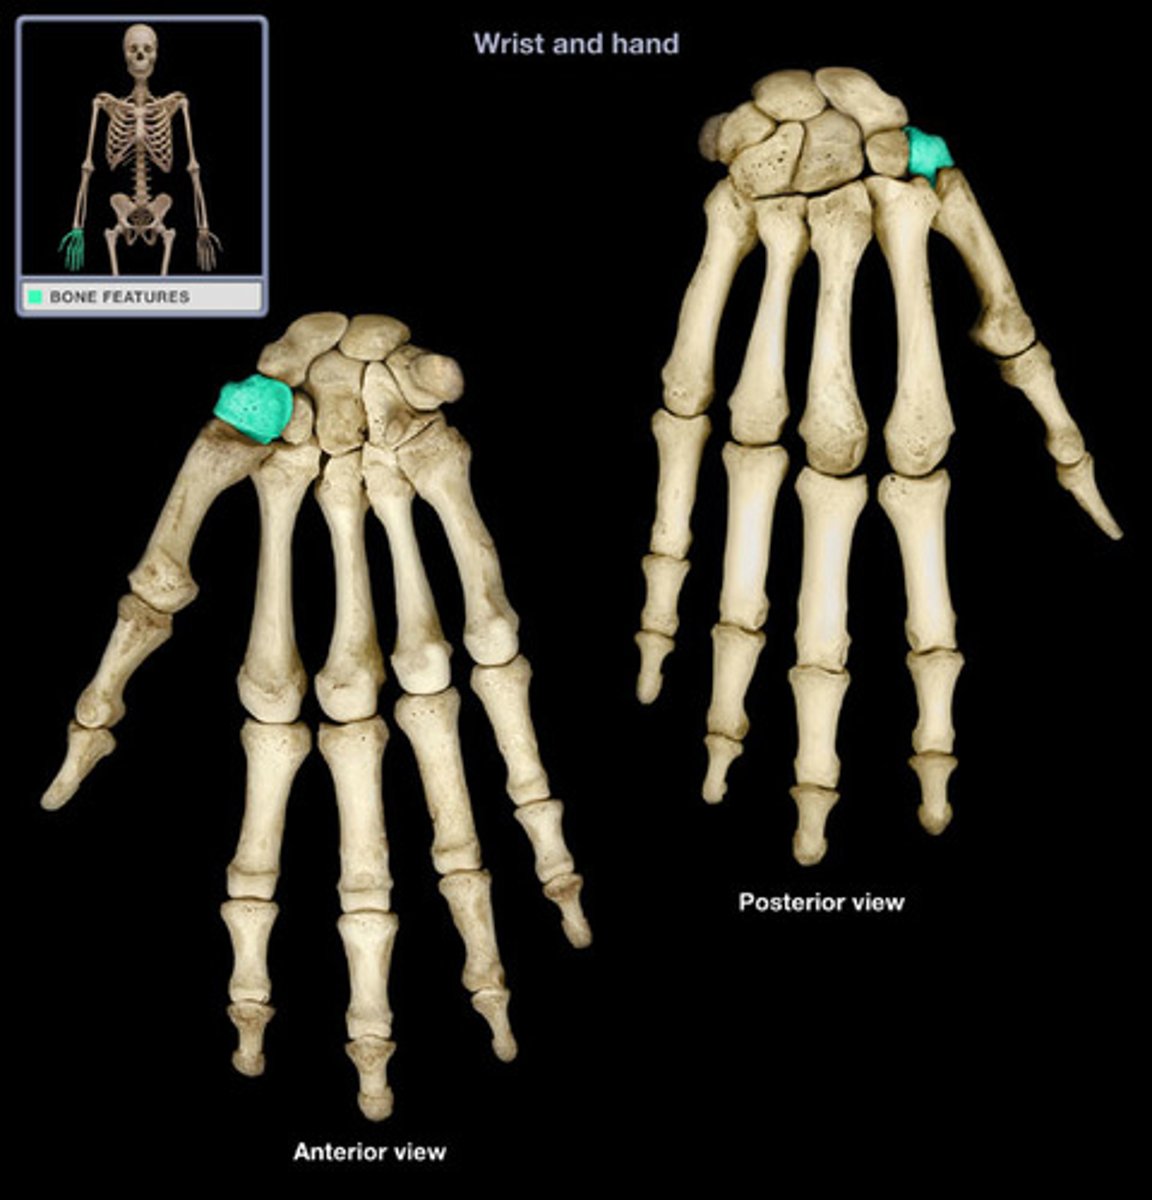

Carpal bones

scaphoid, lunate, triquetrum, pisiform, trapezium, trapezoid, capitate, hamate

Pisiform

Name this specific bone of the hand.

Trapezium

Name this specific bone of the hand.

Trapezoid

Name this specific bone of the hand.

Capitate

Name this specific bone of the hand.

Hamate

Name this specific bone of the hand.